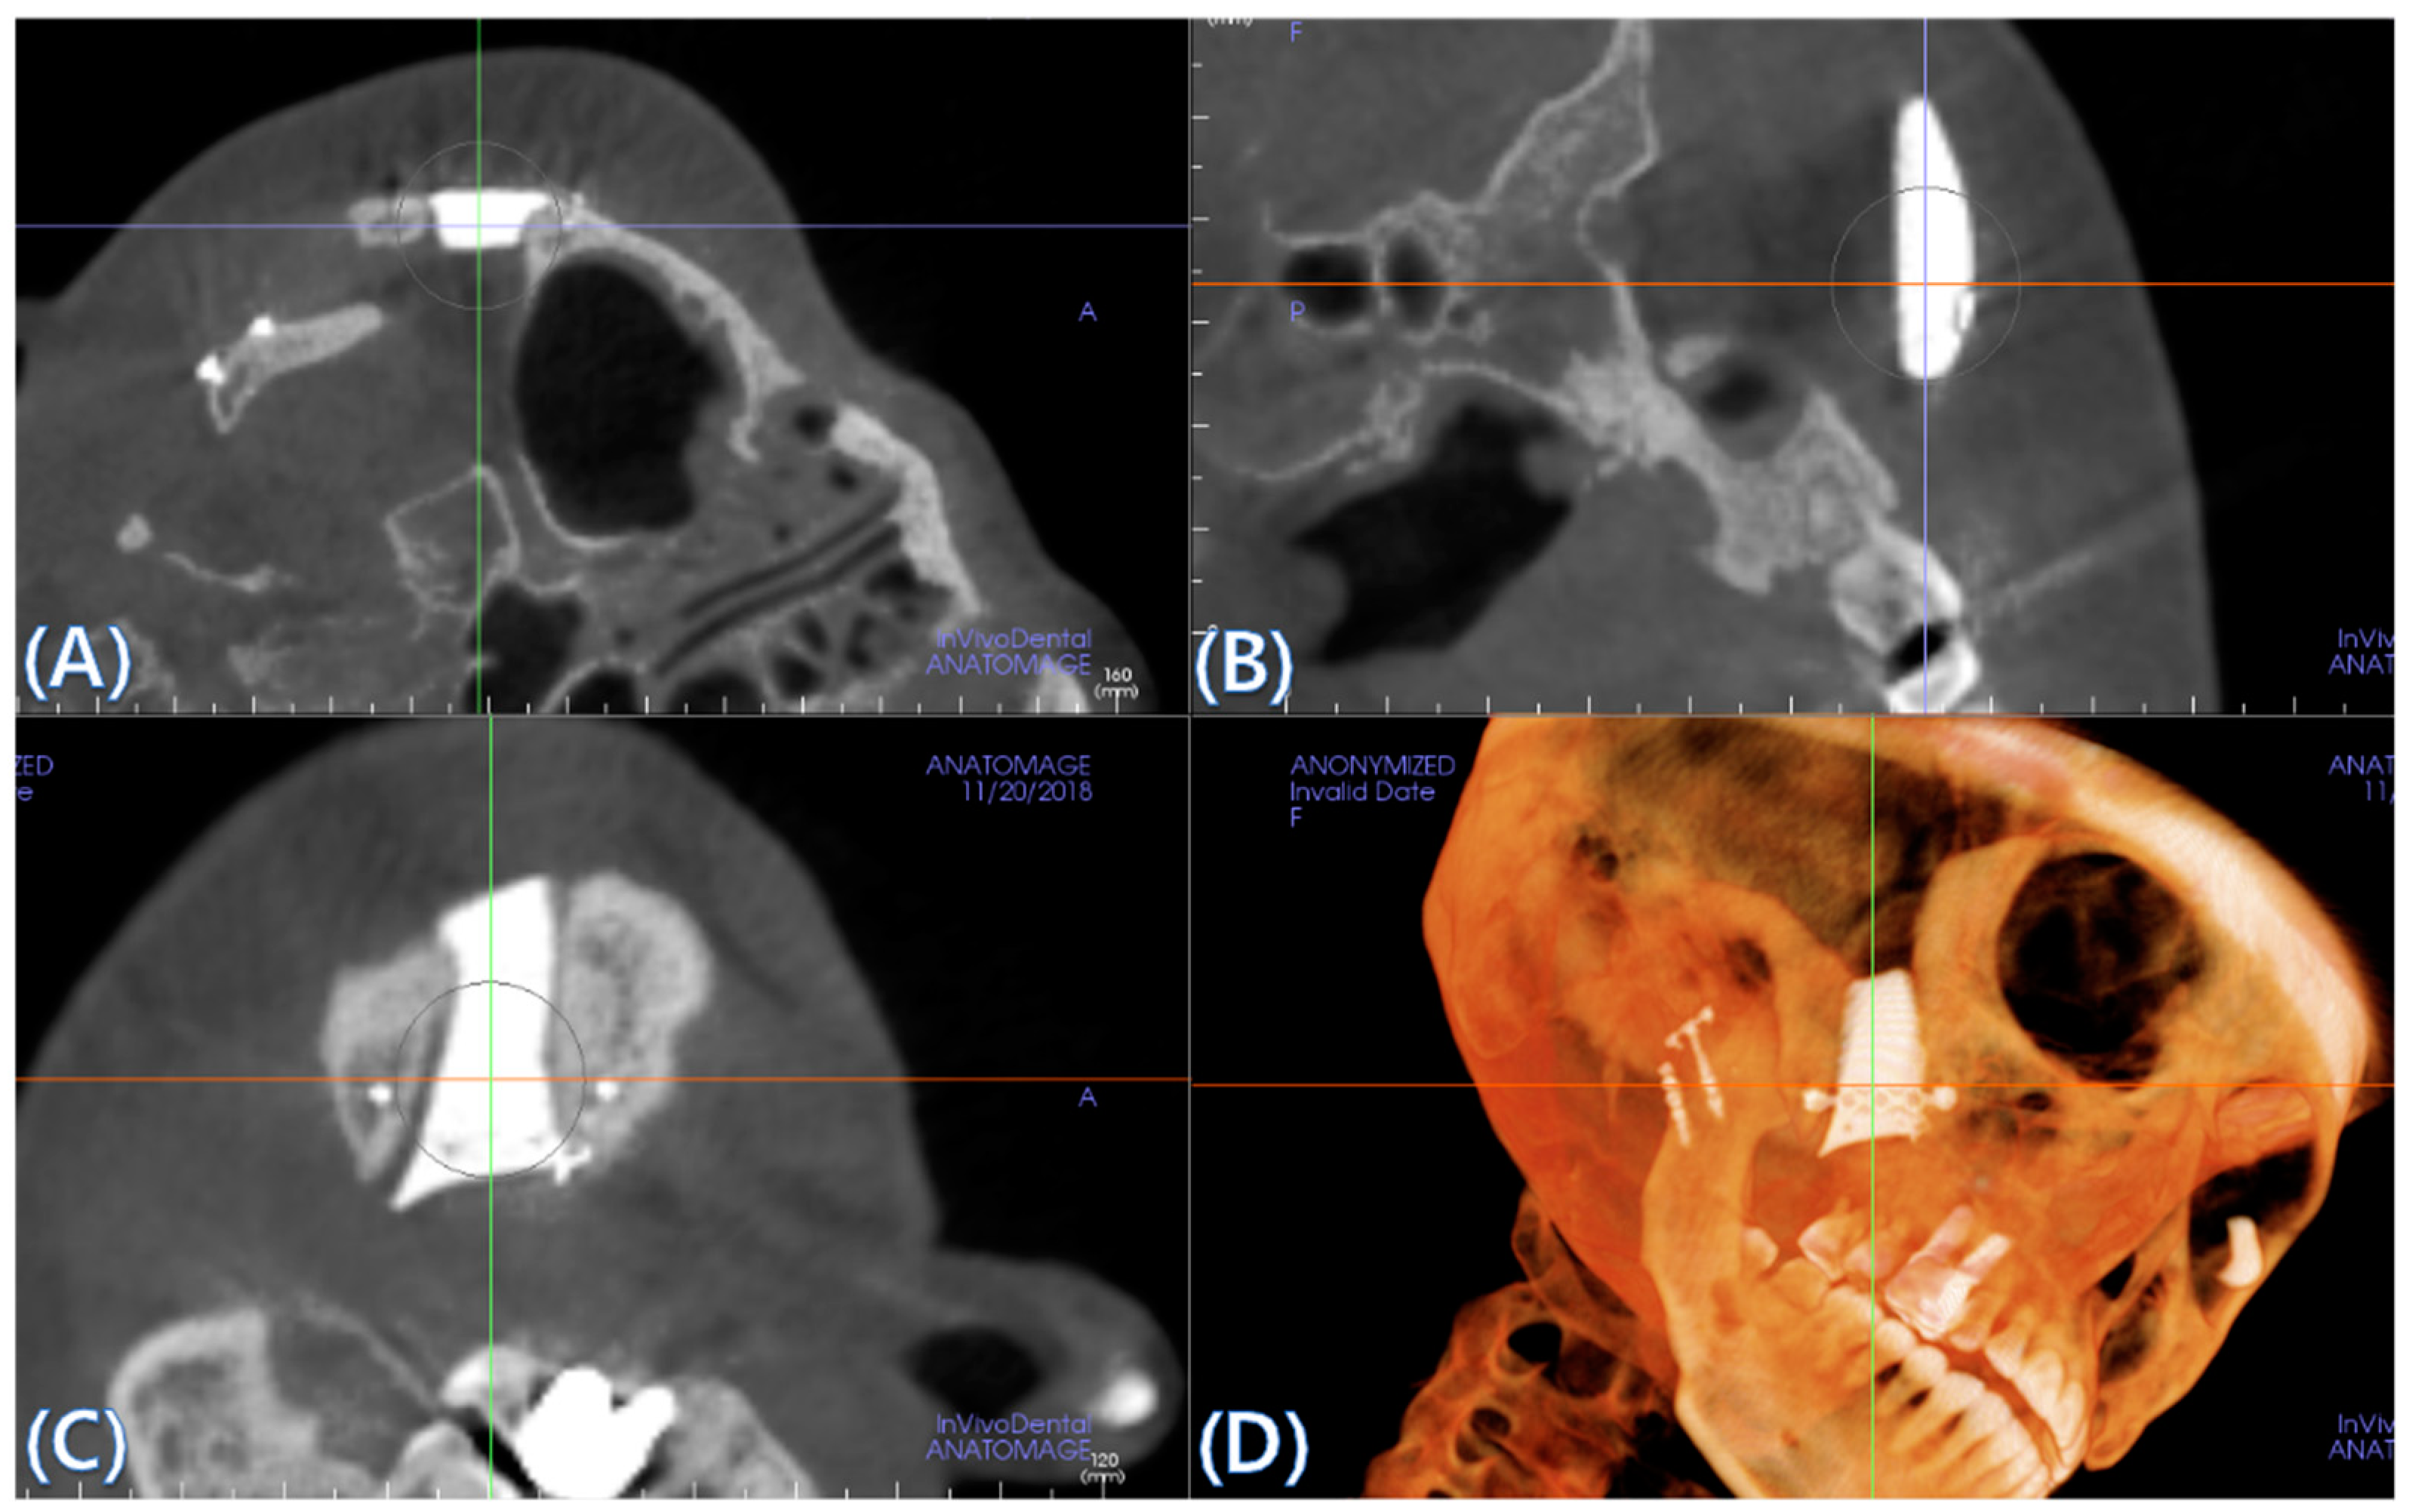

2.5. Cone Beam CT and 3D Comparison

3.2. Fusion Rate Analysis Using 3D CT